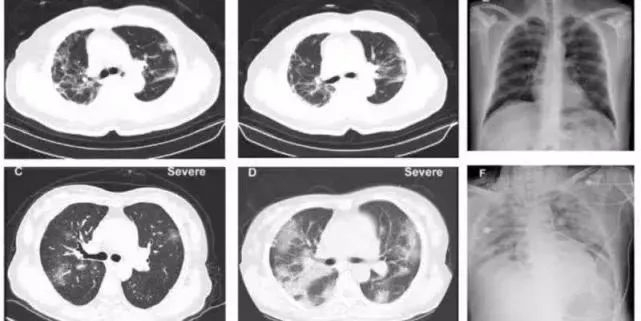

他觉得病理解剖就像是打仗之前要去前沿阵地进行侦查,了解敌人的军种、兵种、火力之后才能打好仗。无论影像学怎么样检查,最后还是要靠细胞学才能确定疾病的真相。

“做CT就像隔着玻璃在看,和遥感卫星一样,它可以看到有一片森林,但森林里面藏着什么东西,基本上没有办法识别。”

· 医生查看新冠肺炎患者CT图像。· 医生查看新冠肺炎患者CT图像。